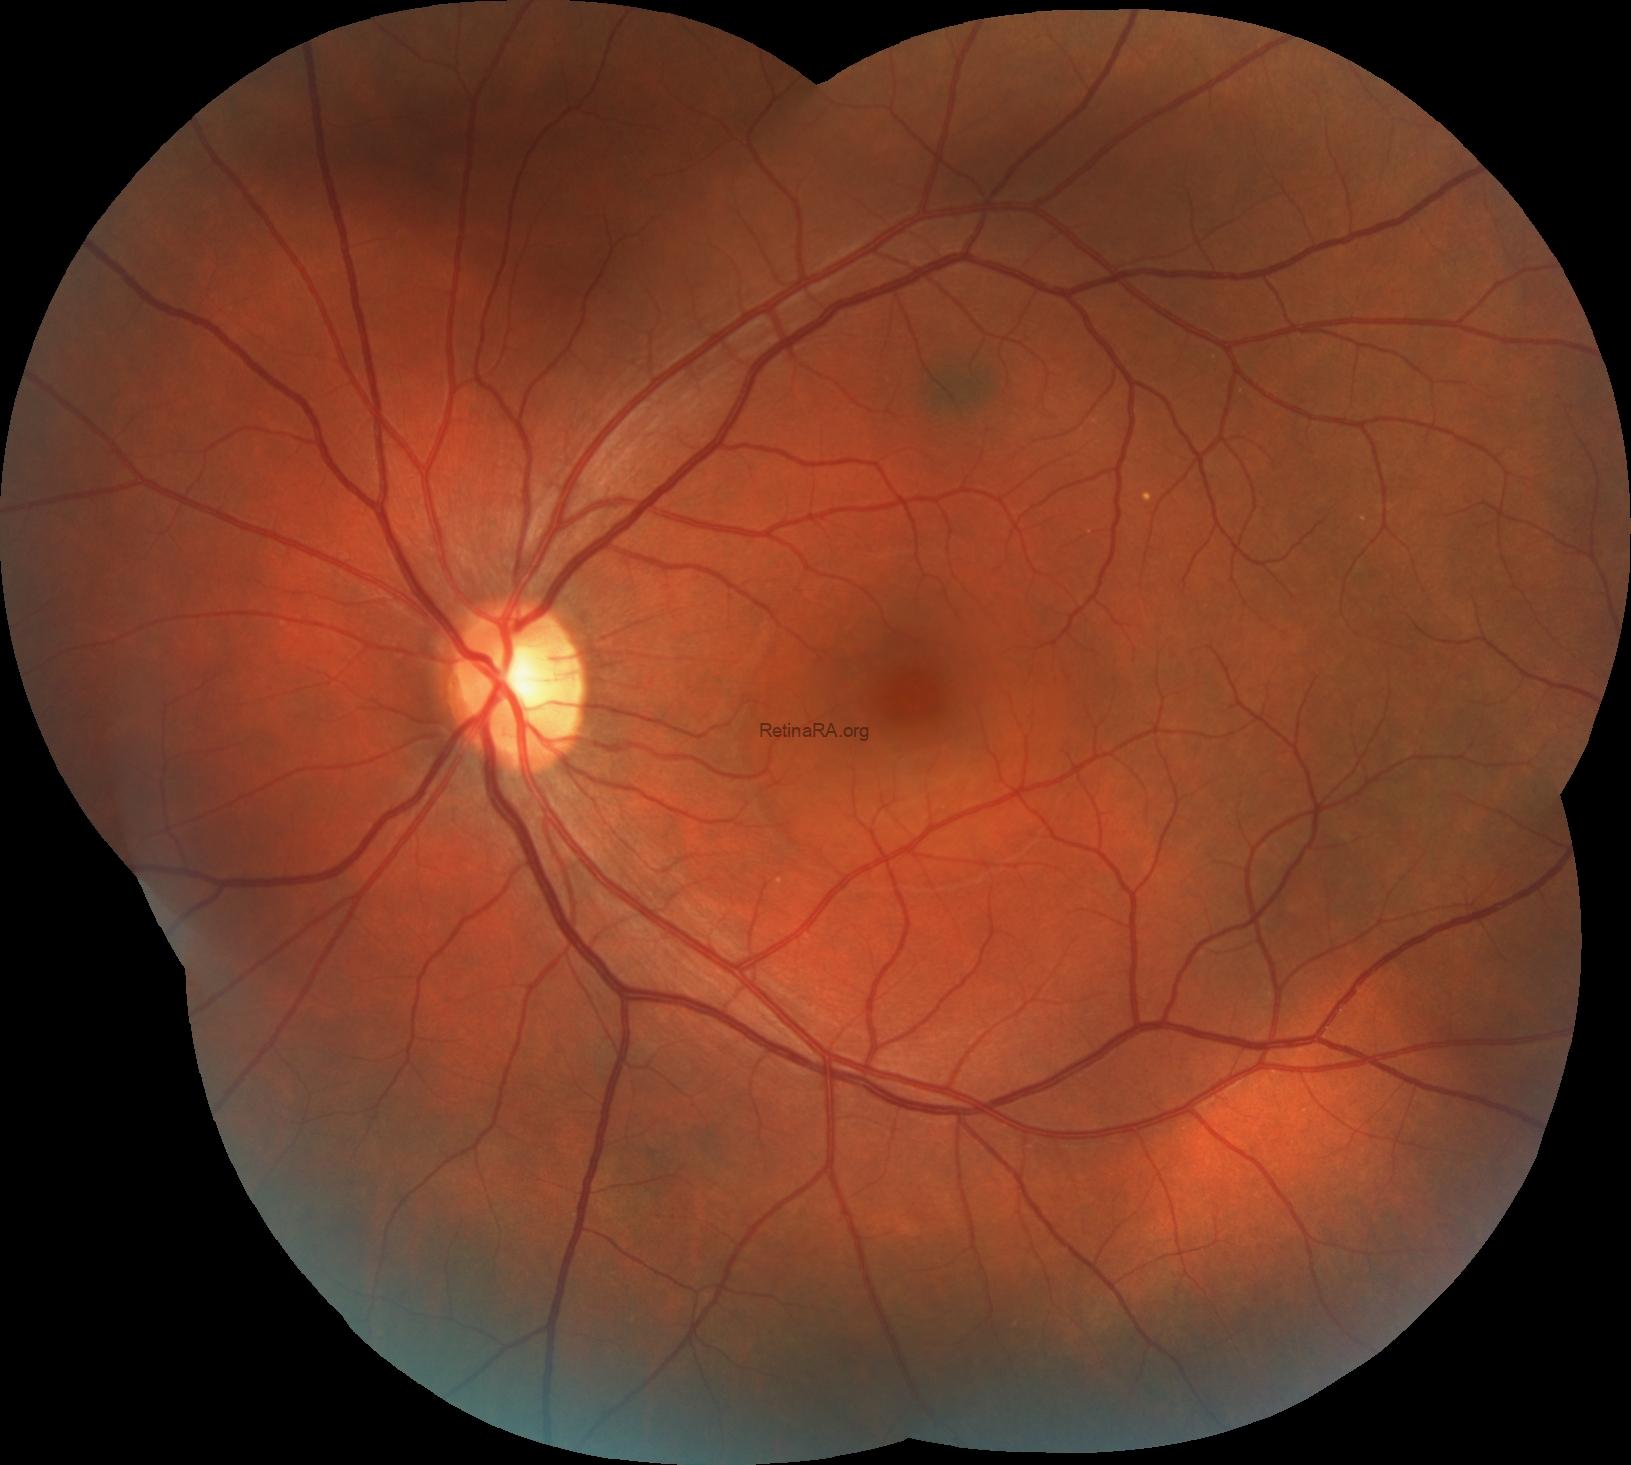

Fundus images of the left eye showed the abnormal foveal reflex with an area of retinal elevation consistent with subretinal fluid in the central retina. Additionally, a choroidal nevus located superior of the fovea was also noted. The right was completely normal.